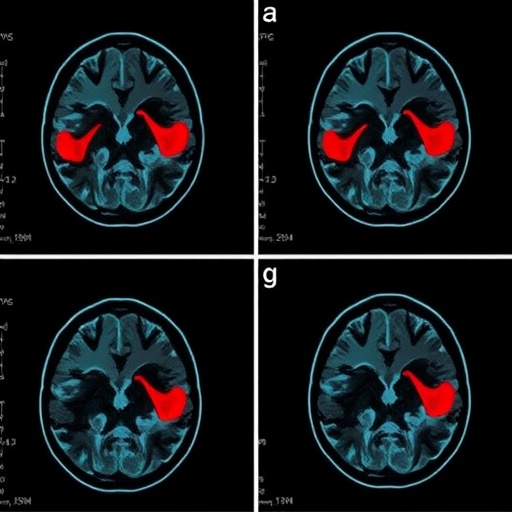

Advancements in neuroimaging to identify salvageable brain tissue, such as perfusion-diffusion MRI mismatch or CT perfusion techniques, have been pivotal. By refining patient selection criteria to those with potentially reversible ischemic penumbra, clinicians can tailor thrombolytic therapy more effectively, maximizing benefits while limiting adverse events.